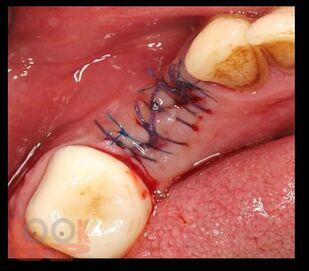

В предлагаемом учебном пособии рассмотрены основные вопросы местного обезболивания, применяемого в стоматологической практике на амбулаторном прием. Приведены характеристики современных местноанестезирующих препаратов и пути их введения. Описаны и продемонстрированы в иллюстрациях ряд хирургических стоматологических операций.